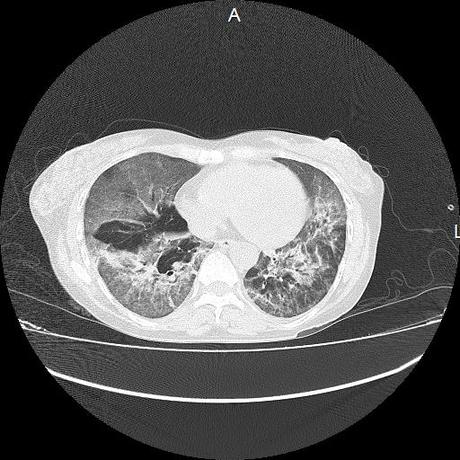

El parénquima pulmonar con areas parcheadas difusas en vidrio despulido combinadas con otras areas hipodensas de baja atenuación debidas a atrapamiento aéreo y engrosamiento intersticial y zonas de fibrosis de predominio en lóbulos medios e inferiores de ambos pulmones.

- LOS HALLAZGOS PUEDEN ESTAR EN RELACIÓN A NEUMOPATIA INTERSTICIAL PROBABLE ETIOLOGIA HIPERSENSITIVA VS AUTOINMUNE/BACTERIANA/FUNGICA.